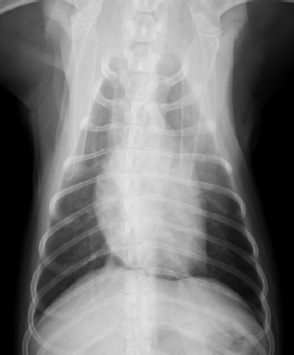

[ レントゲン検査 ]

一般的に心臓が悪くなってくると循環が悪くなり心臓が大きくなります。さらに状況が悪くなると肺に水が溜まったり(肺水腫)、胸の中やお腹に水が溜まったりします(胸水、腹水)。

これらの状況を確認するためにレントゲン検査が必要なります。

[ レントゲン画像サンプル 左;正常、右;心拡大・肺水腫 ]